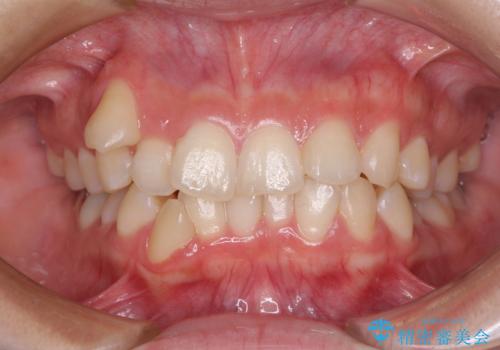

[前歯のねじれ・がたつきを治したい ]ワイヤーとマウスピースの併用矯正治療

![[前歯のねじれ・がたつきを治したい ]ワイヤーとマウスピースの併用矯正治療の症例 治療前](https://seimitsushinbi.jp/wp/wp-content/uploads/2023/11/IMG_0010-1-500x350.jpg?v=1699509973)

![[前歯のねじれ・がたつきを治したい ]ワイヤーとマウスピースの併用矯正治療の症例 治療後](https://seimitsushinbi.jp/wp/wp-content/uploads/2023/11/1c93ab7139a768f1f61b6dd35aac7324-500x350.jpg?v=1699510065)